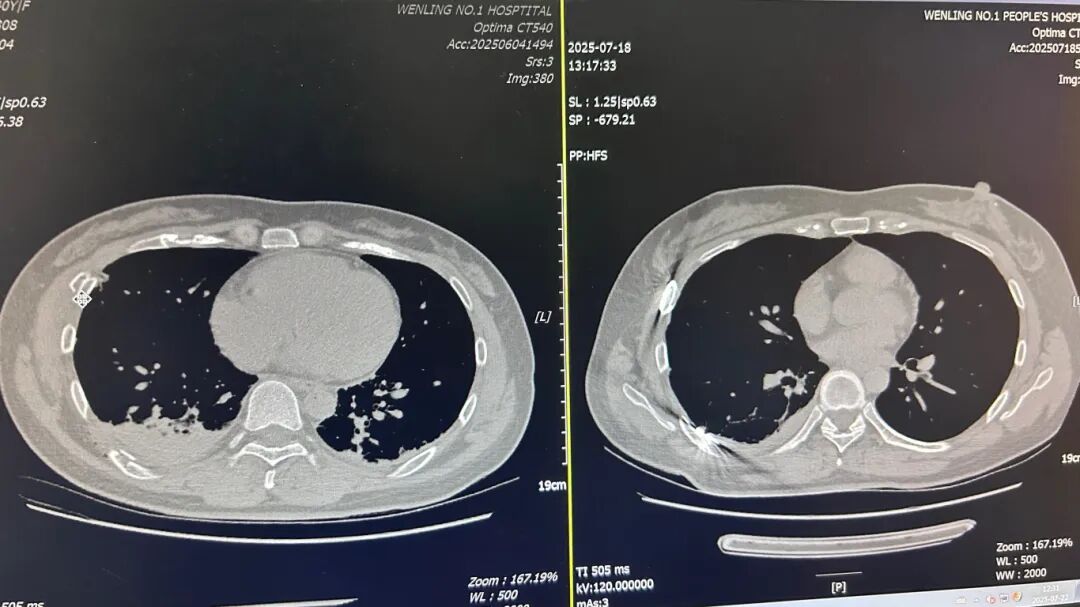

患者因外伤导致多根肋骨骨折,其中部分肋骨断端移位明显,合并胸腔内少量积液,病情复杂。若单纯采用胸腔镜微创手术,对于靠近胸骨、肩胛骨等特殊部位的骨折,操作空间受限,固定难度较大;若完全采用传统开放手术,又会造成较大创伤,不利于术后恢复。

针对这一情况,胸外科团队经过术前缜密评估,制定了“分区施策”的手术方案:

- 开放区:对于位于前胸壁骨折位置相对表浅的肋骨,精准定位肋骨骨折断端,通过1个3厘米的小切口,利用腔镜的高清视野精准定位断端,植入常规肋骨钉完成固定,全程无需大范围切开胸壁组织,最大限度减少创伤;

- 胸腔镜微创区:对于靠近脊柱及肩胛骨开放手术暴露困难的区域,直接利用开放区已切开的3cm切口,置入胸腔镜,利用腔镜的高清视野精准定位断端,植入特制的腔镜下肋骨钉完成固定,全程无需再增加新的切口,最大限度减少创伤;

两种技术的协同配合,既实现了多数骨折的微创处理,又确保了复杂部位的固定效果,手术全程仅用2小时,出血不足50毫升。